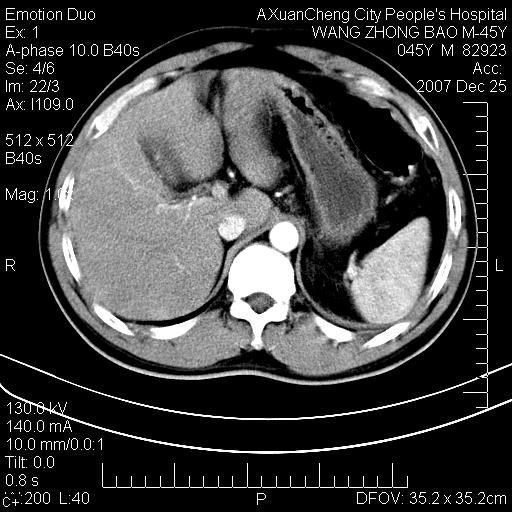

以下是引用qiuleiyu在2007-12-25 18:14:00的发言:[br]胰腺增大,周边渗出改变,肾前筋膜明显增厚,示少量积液.胆囊壁毛糙,周边少许渗出,胆总管壁厚,异常强化,然扩张不明显.结合病程急短;考虑;胆管炎,胆囊炎,胆源性胰腺炎可能大,请结合实验室检查及随访.

以下是引用lisihao在2007-12-25 14:23:00的发言:[br]急性水肿型胰腺炎[br]依据:1、胰腺弥漫性肿大,边缘稍毛糙;[br] 2、双侧肾周筋膜增厚,尤以左侧为甚(重要征象)[br] 3、双侧后胸膜增厚(刺激性炎症);[br] 4、结合病史,查血尿淀粉酶应该可以确诊。